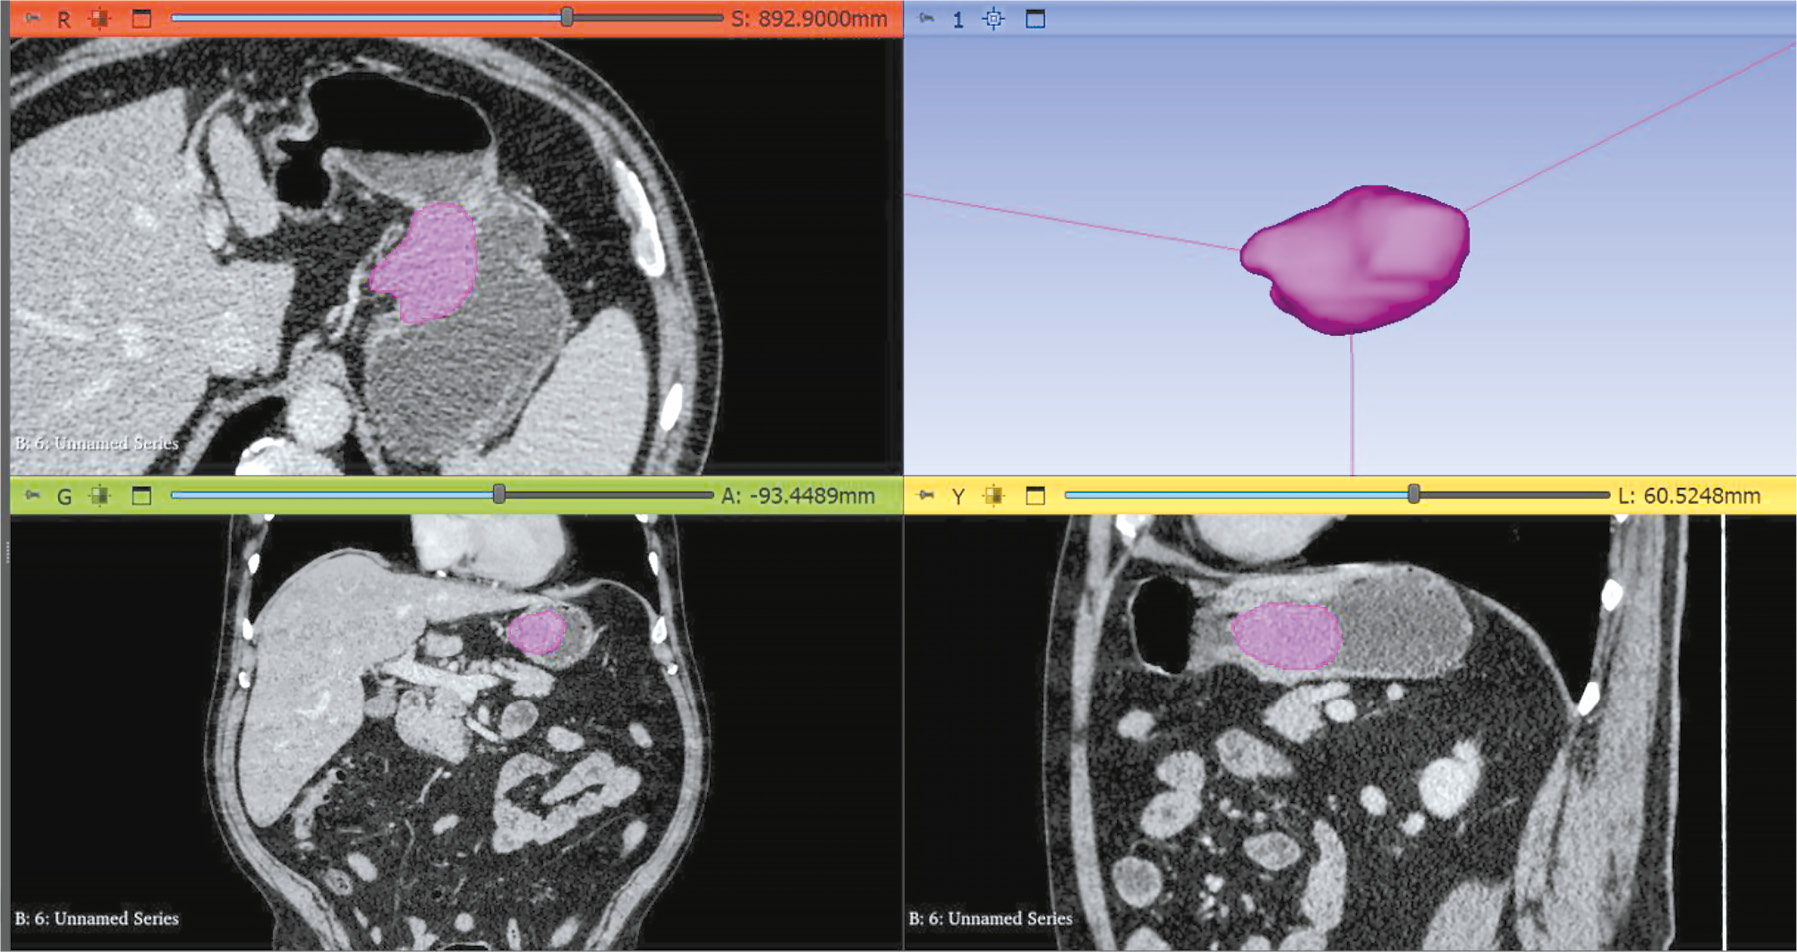

目的。创建一个开放的数据集,包含计算机断层扫描血管造影图像,并对腹主动脉的正常、扩张、血栓形成及钙化情况进行分割。

材料与方法。根据人工智能算法测试方法学,制定了数据集准备的技术任务,计算了所需的样本量,并获得了独立伦理委员会的批准。为了创建数据集,采用了之前开发的基于Slicer 3D软件的半自动分割算法。纳入标准:计算机断层扫描血管造影或腹部计算机断层扫描(含造影)结果;具备动脉相扫描;切片厚度 ≤ 3 mm。排除标准:主动脉腔内存在异物;主动脉夹层。该算法在从Unified Radiological Information System中获取的患者研究结果上进行了验证。并对获得的结果与已制定的要求进行了专家评估,同时评估了使用该分割算法所需的时间。

结果。根据要求计算出的样本量为100个包含动脉相扫描且层厚≤1.2 mm的血管造影研究结果。人群数据:独立患者数量为100人,女性患者占比51%;患者年龄中位数为62岁,年龄范围从18岁到84岁不等。61%的病例发现病变(包括联合病变):其中,60个病例表现出钙化迹象,18个病例表现为主动脉扩张,另外18个病例显示有血栓形成迹象。采用分割算法处理一个研究结果(100层扫描)所需的平均时间为0.8小时。

结论。创建了一个包含100个计算机断层扫描血管造影结果的数据集,数据集包含腹主动脉腔的正常、扩张、血栓形成及钙化的分割结果。该数据集已开放,可以用于人工智能算法的开发和测试,以及腹主动脉的类人建模。